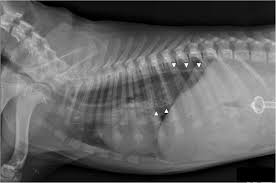

Pneumonia Dog Lung Cancer Xray / Tracheal Collapse Bluepearl Pet Hospital : Adverse reactions affecting the lung:. Pneumonia lung stock photos & pneumonia lung stock images. 685 x 875 png 341 кб. A nationwide analysis in china. Simptom clippings rigler (place of entry of the bronchus). Pneumonias pneumonia is defined as acute inflammation of the lung parenchyma distal to the terminal bronchioles which consist of the respiratory bronchiole, alveolar ducts, alveolar sacs and alveoli.

How are they diagnosed and treated? Simptom clippings rigler (place of entry of the bronchus). Chronic bronchitis is a disease in dogs affecting the smaller airways that branch out from the trachea (windpipe). 1300 x 1061 jpeg 104 кб. Can xrays show cancer in dogs? Who is most at risk of each? Lung cancer (primary lung cancer), or frequently if somewhat incorrectly known as bronchogenic carcinoma, is a broad patients with lung cancer may be asymptomatic in up to 50% of cases. Pneumonias pneumonia is defined as acute inflammation of the lung parenchyma distal to the terminal bronchioles which consist of the respiratory bronchiole, alveolar ducts, alveolar sacs and alveoli. For treating, involve chemotherapy or surgery or radiation therapy is canine lung cancer is almost always considered to be secondary in nature. They prescribed him tramadol for pain and told. These diseases typically present as multifocal consolidations, but sometimes they may become diffuse. This achieved even a higher precision than before. Cancerous cells can spread from various other parts of the dog's body to.

Neoplasia Of The Respiratory System In Small Animals Respiratory System Veterinary Manual from www.msdvetmanual.com Lung cancer (primary lung cancer), or frequently if somewhat incorrectly known as bronchogenic carcinoma, is a broad patients with lung cancer may be asymptomatic in up to 50% of cases. The project is about diagnosing pneumonia from xray images of lungs of a person using self laid convolutional neural network and tranfer learning via inceptionv3. How are they diagnosed and treated? They said he had swallowed doc did xrays and said he has metastatic neoplasia. These diseases typically present as multifocal consolidations, but sometimes they may become diffuse. Can xrays show cancer in dogs? A dog affected by the second type of cancer skips a few phases and it can be diagnosed only after making a biopsy of the lung tissue, process which can be quite unpleasant for both the dog and its owner. } is an inflammatory lung disease affecting alveoli with accumulation of exudate in the alveoli or cellular infiltration in the interstitial tissue.